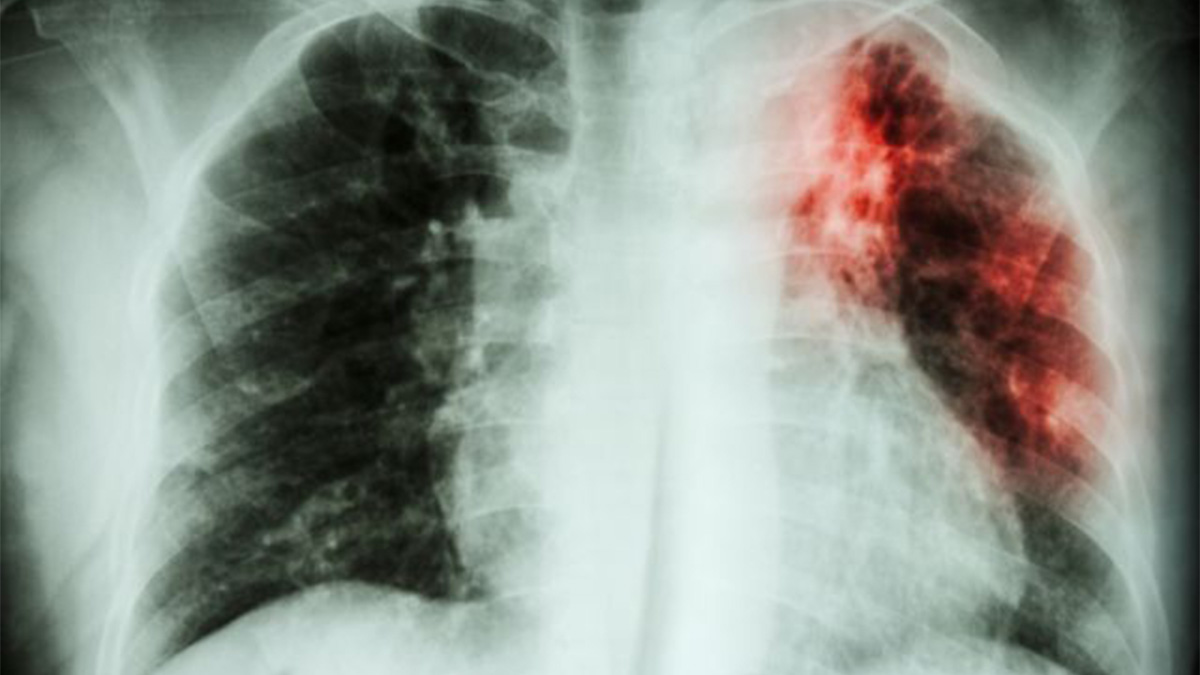

Plus de 11 800 cas de tuberculose, dont 336 décès, ont été recensés en 2023 dans la province de l’Ituri. Cette maladie continue de se propager dans la région en raison de l’accès difficile aux soins, notamment à cause de la destruction ou de l’incendie de nombreuses structures sanitaires par les groupes armés.

Ces informations ont été révélées mercredi 10 juillet par le Programme Lèpre et Tuberculose lors d’une matinée scientifique organisée à l’Université Shalom de Bunia. Selon le Dr Justin Mukonkole, coordonnateur du programme, la difficulté d’accès aux structures sanitaires, dont la plupart ont été incendiées ou détruites par les milices, est la principale cause de la propagation de la tuberculose en Ituri.

Une forte prévalence de la maladie est observée dans les zones minières, qui représentent environ 50% des patients. Les zones de santé les plus touchées sont Bambu, Nizi, Mangala, Mongbwalu (territoire de Djugu), Bunia et Rwampara (territoire d’Irumu), et Nia Nia (territoire de Mambasa). Parmi les patients tuberculeux en Ituri, on compte environ 1 200 enfants. Le nombre de cas en augmentation constante

Le Dr Mukonkole souligne que le nombre de malades ne cesse de croître à cause des difficultés d’accès aux soins. En effet, plusieurs structures sanitaires dédiées à la prise en charge de la tuberculose ont été détruites ou incendiées par les milices. D’autres ne sont pas opérationnelles en raison de l’insécurité persistante.